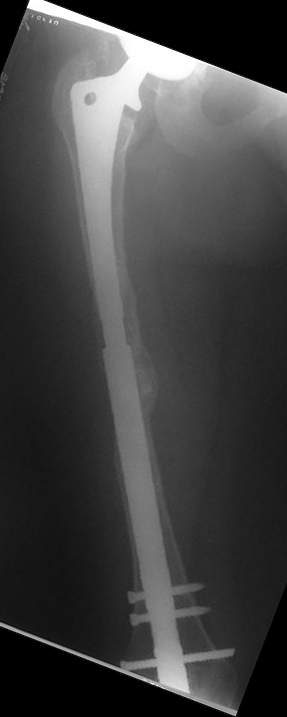

Female, rheumatoid, THA in 2003, car accident in 2006, failed plating. Nailing in Oct 2007. The nail is solid with hollow proximal part where the stem is docked. Last images are in 1 year after

nailing.

The femur responded by failure to Mennen plating (DePuy Bridge plate). So i would add that the ability to unite is realized in mechanically and biologically sound conditions.